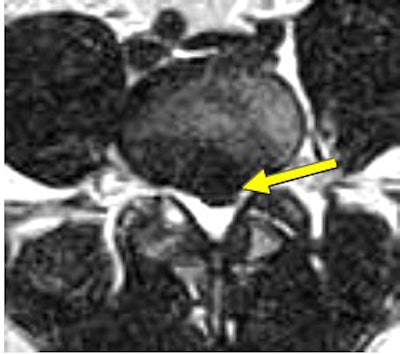

![]() |

| Above, preaxial loaded. Below, axial-loaded image. Central subligamentous disk herniation and discogenic disease at L5-S1 impressing the thecal sac only after axial loading is applied. L4-L5 bulging, discogenic disease, and a central subligamentous disk herniation impressing on the thecal sac. Bulging and discogenic disease at all other levels. |